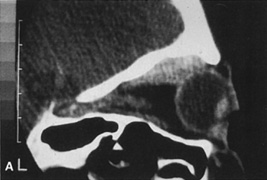

Fig. 14. A,B. Large intraorbital lymphangioma causing proptosis and optic nerve compression

in a 2-year-old child. C. View of the left orbit from above after removal of the frontal bone flap, including

over the superior orbit. The orbital mass is exposed in this fashion. D. The fronto-orbital bone flap is wired back in place after completion of

the procedure. E. Postoperative appearance of the patient. F. The postoperative CT scan shows complete removal of the lymphangioma. This

large and diffuse lesion would have been difficult to remove with